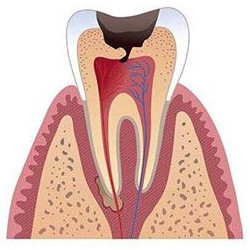

Периодонтит представляет собой воспаление тканей, окружающих зуб. Первый симптом, который появляется при периодонтите - боль при накусывании на больной зуб.

Зачастую причиной возникновения периодонтита является нелеченый пульпит или некачественная пломбировка каналов зуба, если остатки пульпы не были полностью удалены и инфекция начала распространяться за пределы зуба.

• извлечение содержимого корневых каналов;

• механическая и медикаментозная обработка корневых каналов;

• применение препаратов, воздействующих на периодонтит;

• пломбировка корневых каналов;